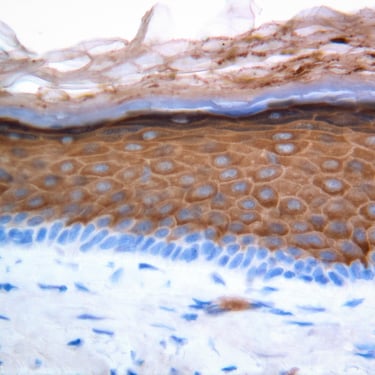

Skin tissues innovation

and testing

Award winning skin tests and the latest skin models for testing cosmetics, drugs and devices